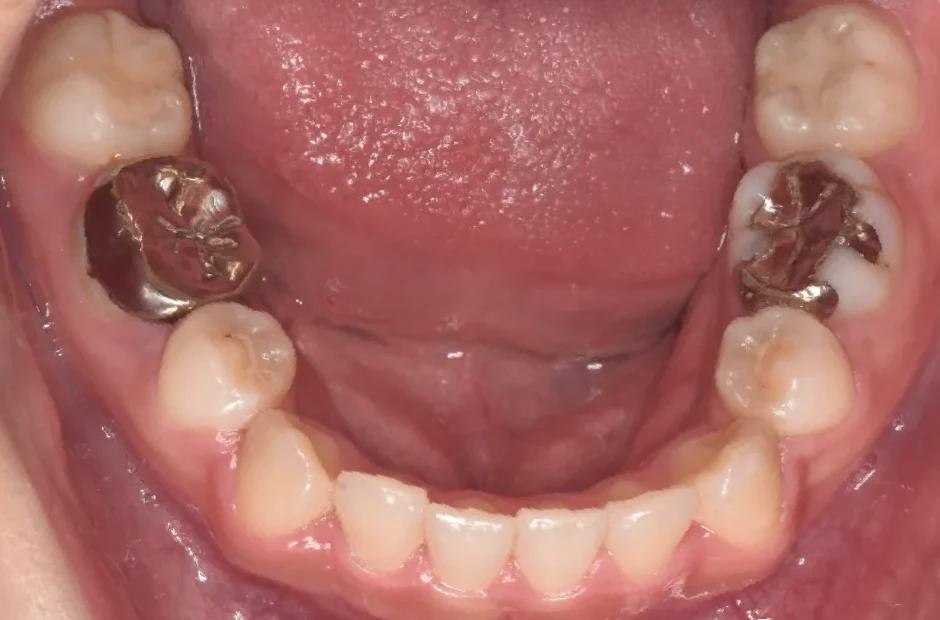

先天欠如

| 診断名・主訴 | 先天欠如 |

|---|---|

| 年齢・性別 | 14歳・女性 |

| 治療期間・回数 | 2年 |

| 治療に用いた主な装置 | ブラケット矯正 |

| 抜歯部位 | なし |

| 治療費 | 60万円(税抜) |

| リスク・副作用 | 装置による違和感・疼痛・歯肉退縮・歯根吸収・虫歯のリスクなど |